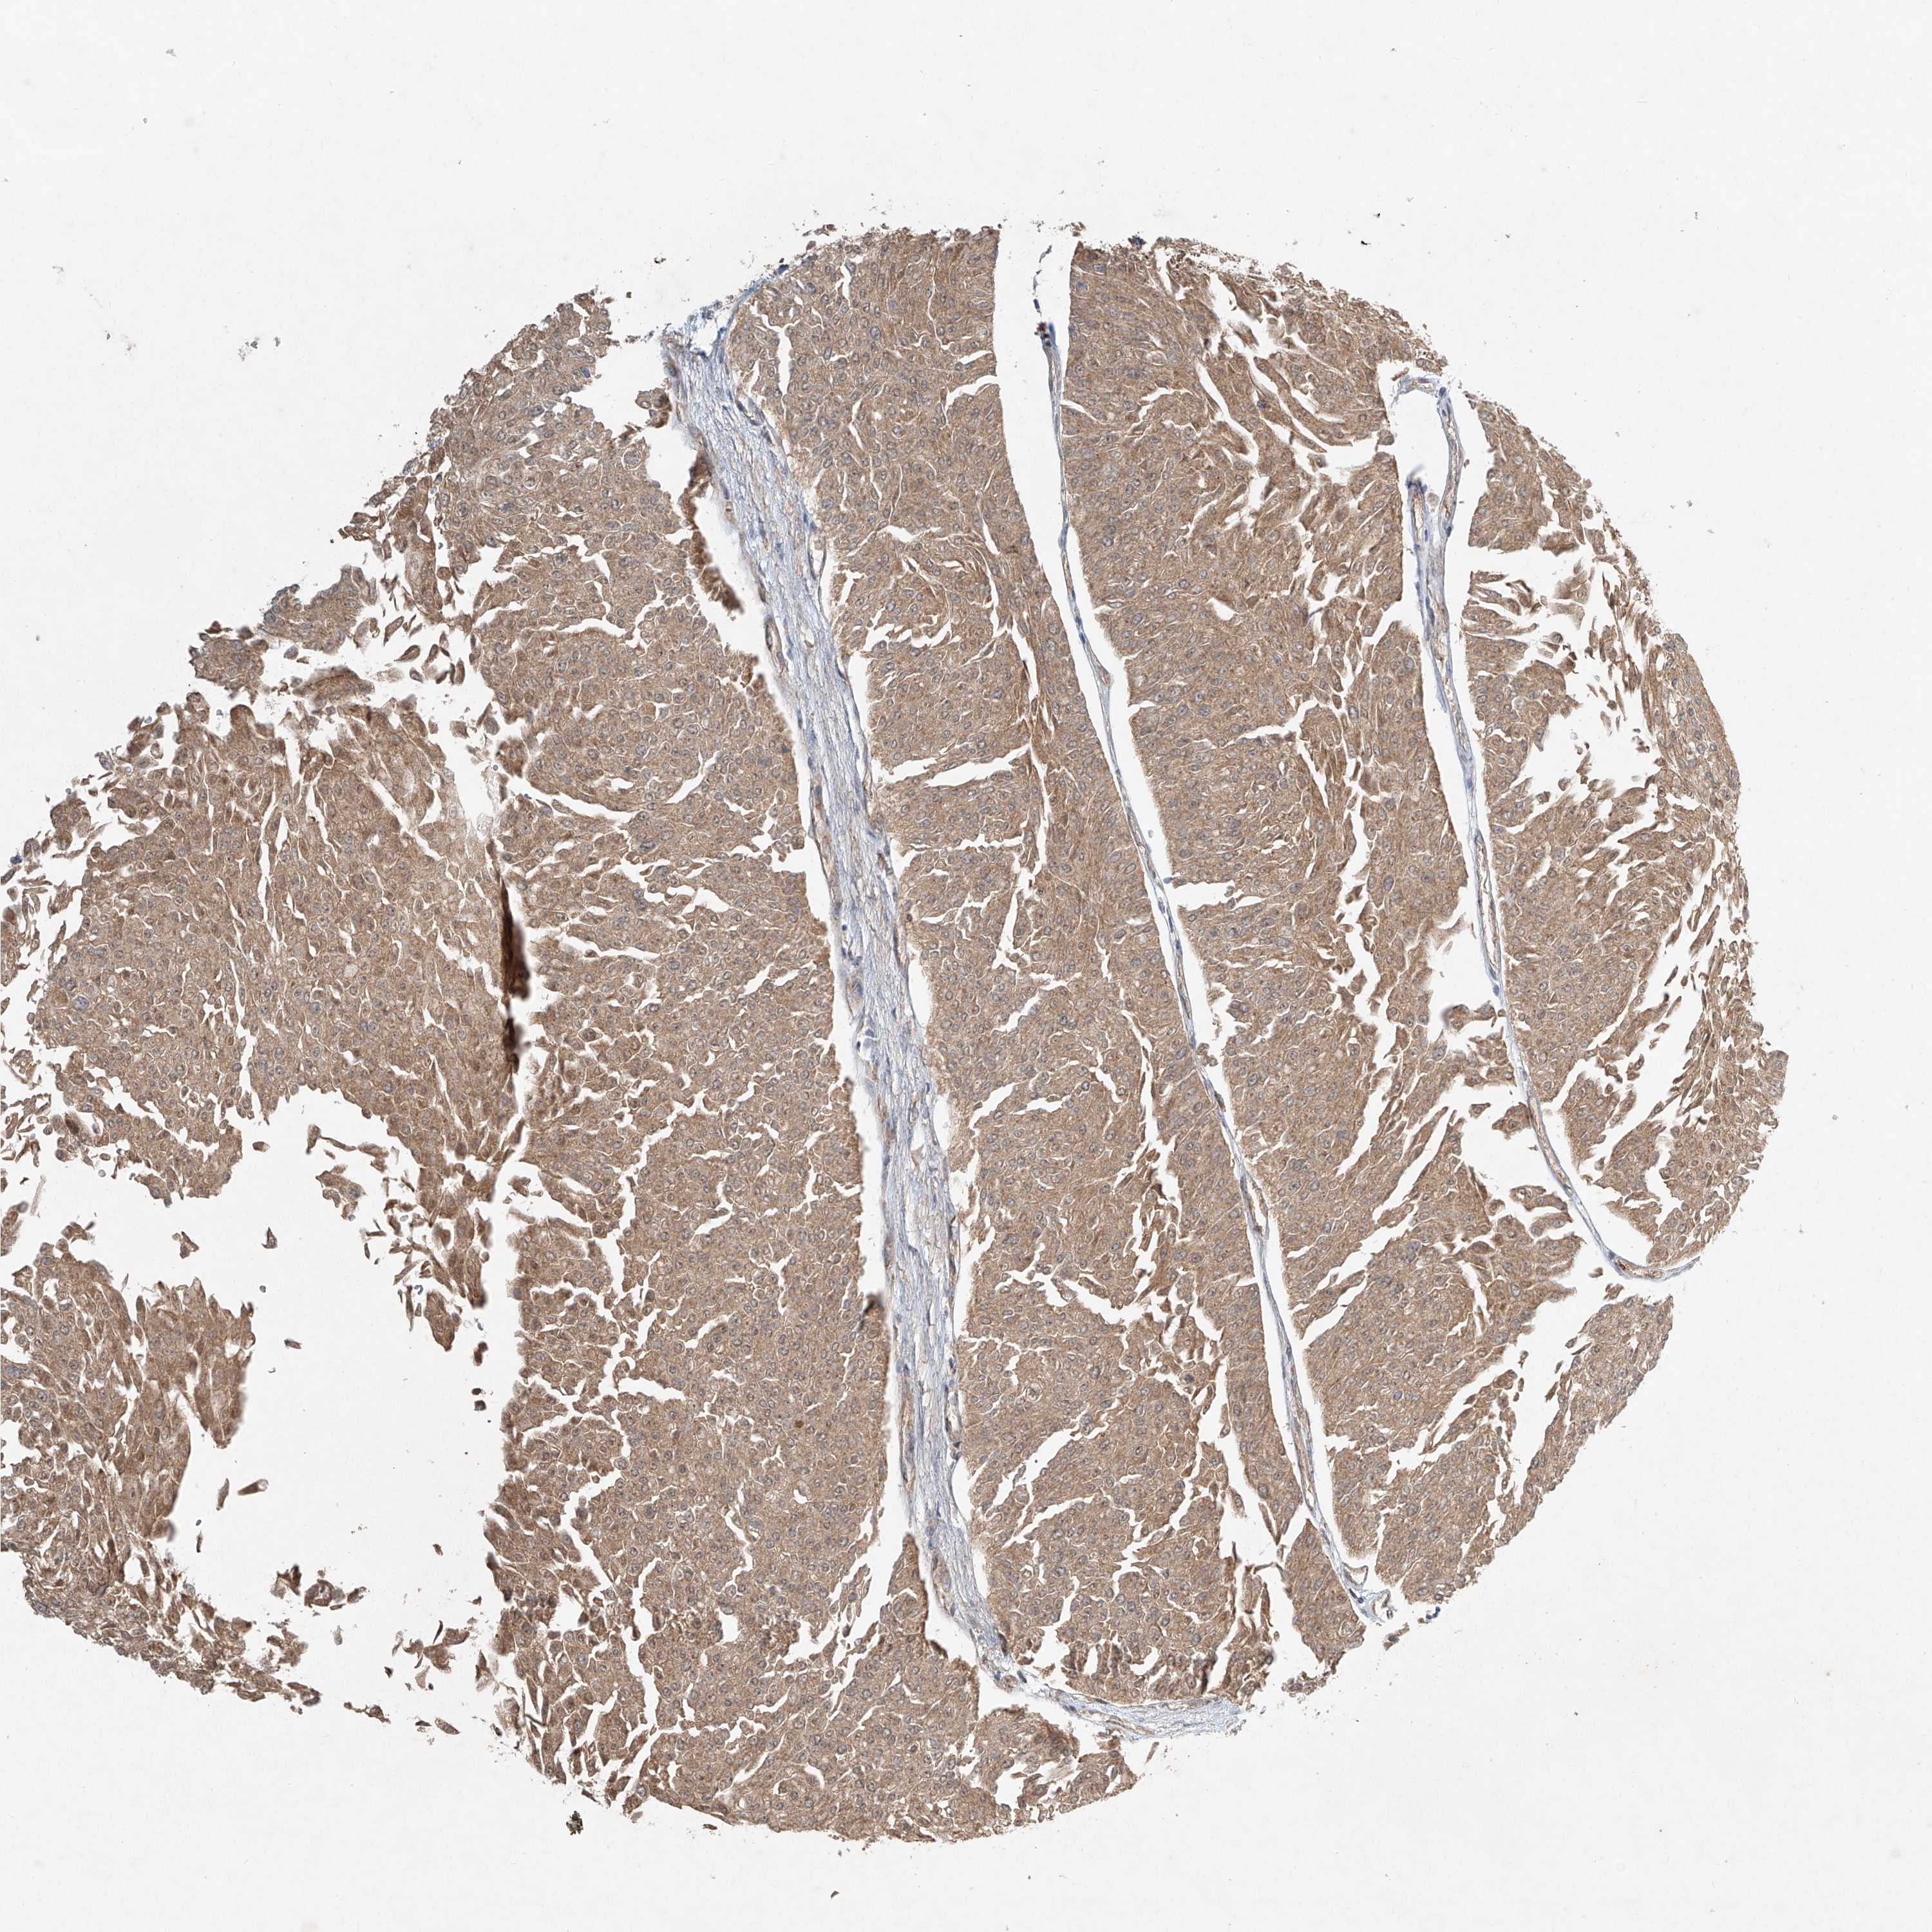

UROTHELIAL CANCER - Protein expressioni

A mouse-over function shows sample information and annotation data. Click on an image to view it in a full screen mode. Samples can be filtered based on level of antibody staining by selecting one or several of the following categories: high, medium, low and not detected. The assay and annotation is described here.

Note that samples used for immunohistochemistry by the Human Protein Atlas do not correspond to samples in the TCGA dataset.

Antibody stainingi

Antibody staining in the annotated cell types in the current human tissue is reported as not detected, low, medium, or high, based on conventional immunohistochemistry profiling in selected tissues. This score is based on the combination of the staining intensity and fraction of stained cells.

Each image is clickable and will lead to virtual microscopy that enables deeper exploration of all samples and also displays staining intensity scores, fraction scores and subcellular localization as well as patient and tissue information for each sample.

Antibody HPA031157

Staining

High

Medium

Low

Not detected

Intensity

Strong

Moderate

Weak

Negative

Quantity

>75%

75%-25%

<25%

None

Location

Nuclear

Cytoplasmic/membranous

Cytoplasmic/membranous,nuclear

Urothelial carcinoma, Low grade

Urothelial carcinoma, High grade